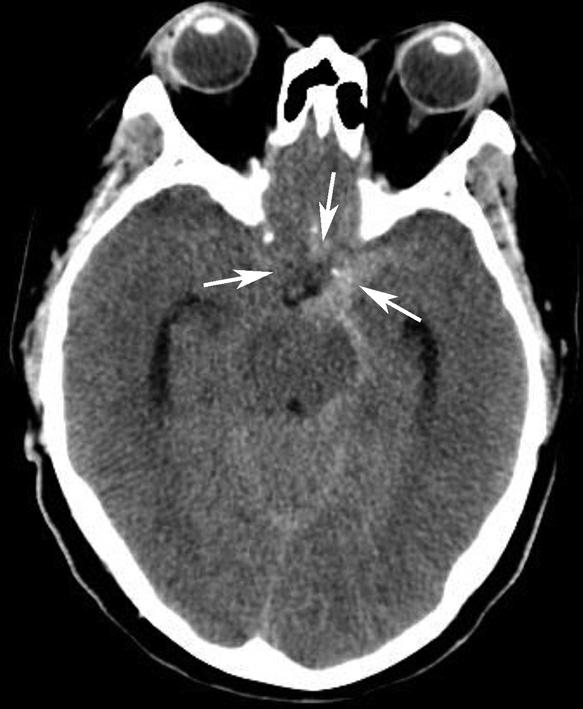

鞍上池位于层面的中部,多数呈六角星形,其前角连大脑纵裂池、两个前外侧角通外侧裂池、两个后外侧角延续为环池,后角为中脑双侧大脑脚之间的脚间池。鞍上池的六条边为前面的两侧额叶底部、外侧边为颞叶钩回,后两条边为大脑脚。如后方为脑桥,则鞍上池呈五角星形。鞍上池内前部有视交叉、视束及漏斗,两侧有颈内动脉。乳头体位于鞍上池后部中脑前方。鞍上池两侧为颞叶,颞叶内侧前部为杏仁体,杏仁体后方为海马,海马内后方向内突出的脑回为海马旁回,海马外侧可见侧脑室颞角。在颞叶前方通过外侧裂池与额叶相隔。鞍上池后方为中脑、中脑后部的中脑导水管及中脑两侧的环池。

鞍上池是该层面需要重点观察的部位。其形态及密度的改变均提示病变(图1-2-18、图1-2-19),例如鞍上池失去正常五角星或六角星形态、甚至闭塞,或者鞍上池密度升高或不均匀。此外,环池闭塞多见于颅内压严重增高的患者,为诊断脑疝的影像学依据(图1-2-20)。

图1-2-19 鞍上池密度改变

左侧颈内动脉瘤破裂,血液进入鞍上池,导致其密度明显升高(箭)